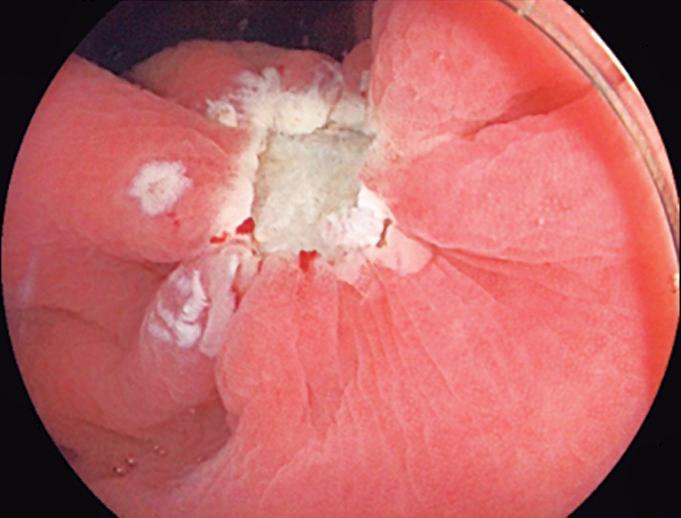

Evaluación endoscópica e histológica

La endoscopía superior es un procedimiento fundamental para el diagnóstico, la evaluación de la respuesta al tratamiento y el monitoreo a largo plazo de la actividad de la EEo. Los hallazgos endoscópicos típicos incluyen edema (reducción de vascularidad), anillos esofágicos fijos, exudados blancos, surcos longitudinales, estenosis, estrechamiento de la luz esofágica, friabilidad de la mucosa (mucosa en papel crepé) y una consistencia firme de la mucosa al realizar biopsias (signo de “tracción" o "resistencia”) en pacientes con fibrosis (Figura 1). Estos hallazgos no son patognomónicos y no constituyen un criterio diagnóstico; sin embargo, cuando se evalúa de forma cuidadosa, en la gran mayoría de los casos se pueden observar.19-21

En el panel A se observa un esófago con edema difuso y pliegues longitudinales; en el panel B se aprecia edema con pliegues y exudados blanquecinos; en el panel C se evidencia un estrechamiento luminal acompañado de anillos esofágicos y exudados; y en el panel D se muestra un desgarro mucoso posterior a la dilatación con bujía de Savary, hallazgo esperado tras este procedimiento terapéutico.

Figura 1. Características endoscópicas de la esofagitis eosinofílica